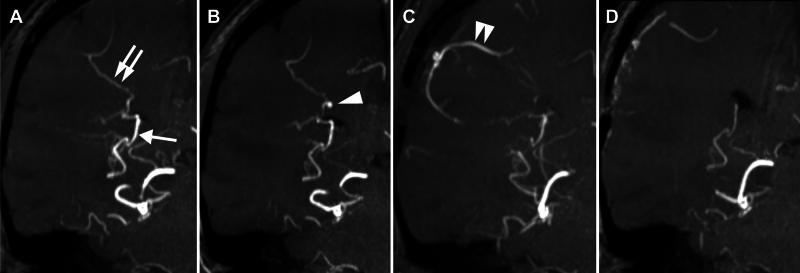

A 29-year-old woman with asymptomatic MMD became pregnant. She had not undergone bypass surgery, and choroidal anastomosis had developed in the right hemisphere. After an uneventful pregnancy for 34 weeks, she suddenly manifested HELLP (hemolysis, elevated liver enzymes, and low platelets) syndrome and underwent an emergency cesarean section. Although both she and her neonate remained healthy, MR angiography after delivery revealed on the choroidal anastomosis a small aneurysm, which had been absent before conception, with the possible finding of minor bleeding. After recovering from HELLP syndrome, she underwent direct bypass surgery, which resulted in the disappearance of the aneurysm and marked reduction of the choroidal anastomosis.

一名29岁无症状MMD女性怀孕。她未接受过搭桥手术,右侧半球出现了脉络膜吻合。怀孕34周期间一切顺利,之后她突然出现HELLP(溶血、肝酶升高和血小板减少)综合征并接受了紧急剖宫产。尽管她和新生儿均保持健康,但产后磁共振血管造影显示脉络膜吻合处有一个孕前不存在的小动脉瘤,可能有轻微出血迹象。从HELLP综合征恢复后,她接受了直接搭桥手术,术后动脉瘤消失,脉络膜吻合明显减少。